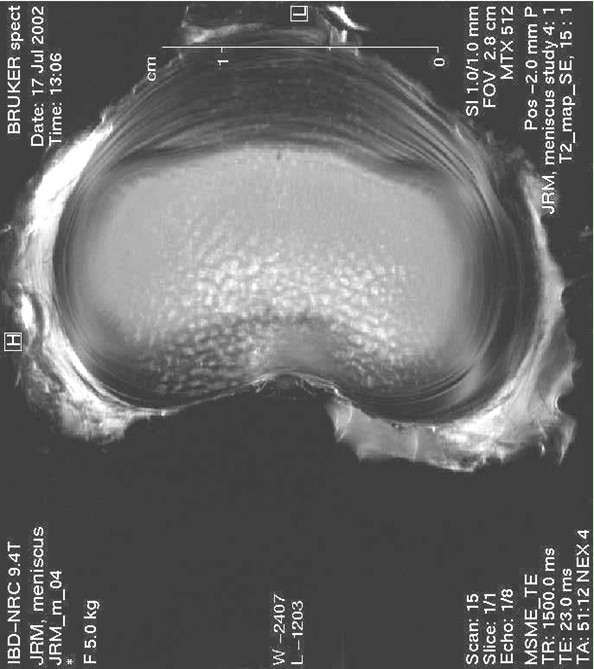

Disc MRI.jpg